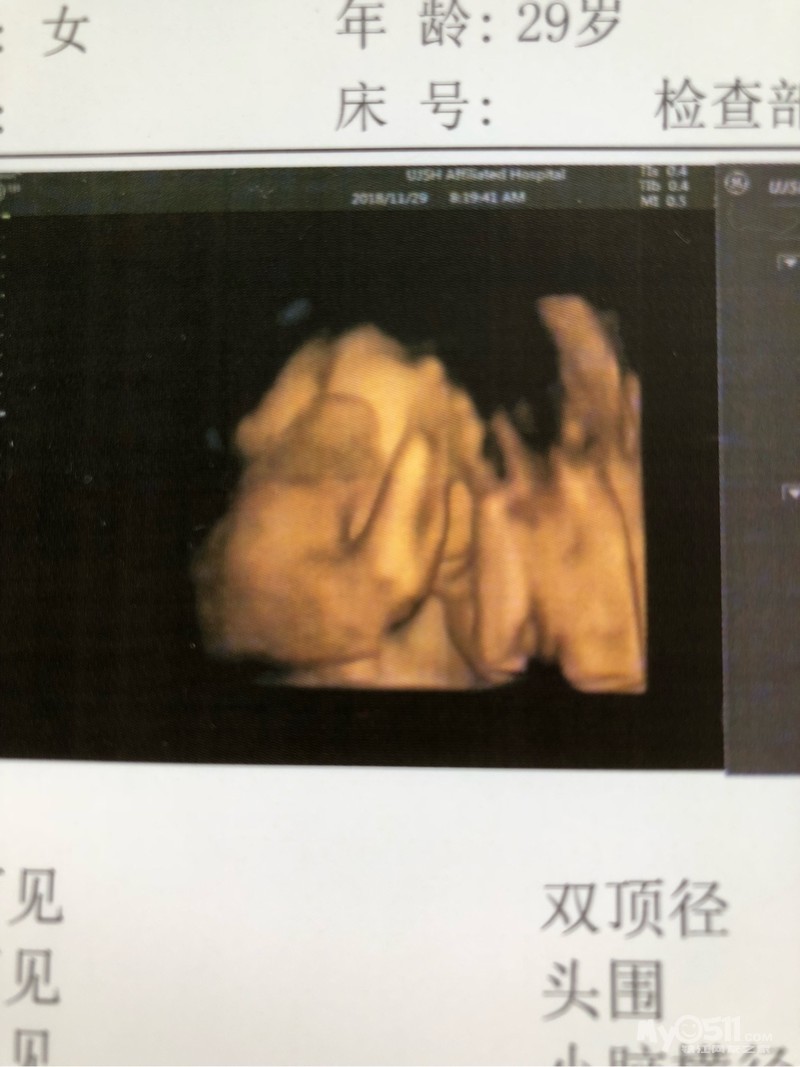

上周四维~一切都正常~开心极了~真是个坚强的宝宝~唯一的遗憾就是没有看到宝宝的脸吧~两只小手各挡了一半脸~真是个害羞的小姑娘~

希望我家小猪妹健康平安地出生呀~